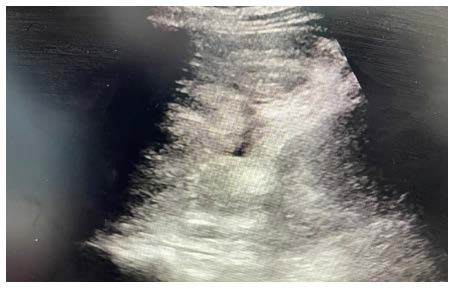

In this case, although eFAST showed free fluid in Morrison’s pouch and splenorenal recess, it failed to localize the bleeding source, demonstrating its limitations in retroperitoneal trauma. This supports the need for clinicians to escalate to WBCT imaging when eFAST findings are inconclusive and clinical suspicion remains high (Figure 1 & Figure 2).

Figure 1: Mass Showing in Mixed Echogenicity

Figure 2: Free Fluid Over Splenorenal Recess